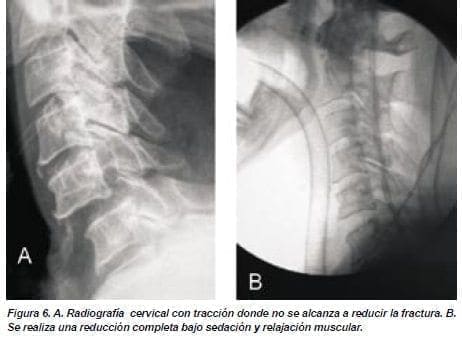

El paciente presentó empeoramiento con aumento del déficit motor en hemicuerpo derecho con parálisis de los músculos dístales en miembro superior derecho. Se decidió realizar tracción cefálica con lo que se redujo un 50% de la luxación en el control a las 12 horas, acompañado de mejoría parcial del dolor y del déficit motor (figuras 5,6). El paciente fue llevado a cirugía donde se le realizó bajo anestesia general y relajación, la reducción completa de la fractura luxación. Se realizó abordaje anterior y se encontró lesión ligamentaria asociada con ruptura del disco intervertebral (figura 7). Se realizó disectomía y artrodesis cervical, injerto de cresta iliaca y una placa #22 entre C5/C6 y se colocó collar cervical permanente (figura 8).

Hay pocos estudios enfocados en el tratamiento de esta lesión, en consecuencia, hay controversia sobre el manejo de estos pacientes.(5,6) El objetivo primario del tratamiento es lograr una preservación de la función neurológica por medio de la reducción del canal, con lo que se logra una descompresión de la medula espinal.(2,8,10,13,17,18) En estos pacientes la reducción cerrada con tracción cefálica es el tratamiento tradicional para el manejo primario (figura 5). La tracción y manipulación manual, tracción craneana con aumento progresivo de peso, manipulación bajo sedación y relajación, y la tracción bajo anestesia general son las técnicas de reducción cerrada.(11,18) Se empieza con una tracción continua con un peso de 10 libras y gradualmente se va aumentando hasta lograr la reducción, se puede llegar a usar hasta 70 libras (figura 5).(18) La reducción cerrada se debe realizar tempranamente y bajo guía fluoroscópica para evitar la sobre tracción.(10)

La eficacia de estos métodos ha sido confirmada pero estas técnicas fallan en algunos pacientes.(6) Cuando no se logra la reducción cerrada con este método se realiza bajo relajación y anestesia general (figura 6).(10) Hay varios reportes sobre aumento del déficit neurológico secundario a una reducción cerrada. Este empeoramiento se relaciona con un aumento de la compresión producida por una hernia discal traumática extruida.(12,14,18,19) En caso de que no se logre la reducción bajo anestesia general se realiza una reducción abierta por un abordaje posterior.(10)